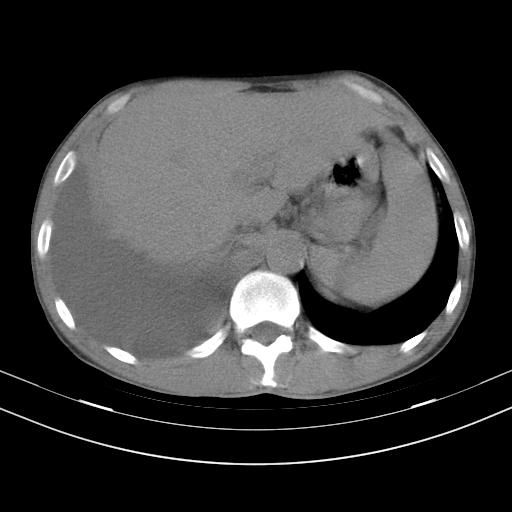

男性,44岁,结核病史多年。现胸闷气短,咳嗽,偶咳血。

1、右侧大量胸腔积液伴右肺压缩性膨胀不全,建议抽液治疗后复查 2、两肺继发性tb伴空洞形成。

1)两肺继发性肺结核伴空洞形成,左肺多发性结核球。2)右侧大量胸腔积液伴右肺部分膨胀不全。3)纵隔淋巴结肿大。

1,双肺多发结节 并空洞影改变, 左侧胸腔积液并部分包裹, 结合原病史首先考虑结核. 但也不除外其它.

2,左侧有一根肋骨陈旧性骨折? 建议追查 .

吉大一院胸水抽检结果:结核性胸水